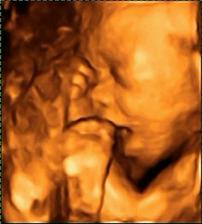

......bude to klučík.....